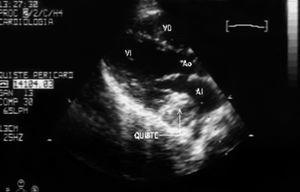

Se presenta el caso de un varón de 12 años de edad, de origen búlgaro, intervenido de hidatidosis cardíaca primaria en surco auriculoventricular derecho hacía 3 años, remitido a nuestro servicio por sospecha de recidiva. Se encontraba asintomático cardiológicamente, y en la exploración únicamente presentaba roce pericárdico en ápex. El electrocardiograma objetivó un ritmo sinusal con bloqueo incompleto de rama derecha y la radiografía de tórax mostraba leve cardiomegalia. El ecocardiograma transtorácico evidenció una tumoración sólida capsulada de 3 x 3 cm de diámetro de contenido heterogéneo que protruía en la aurícula izquierda sin provocar un gradiente hemodinámico significativo (figs. 1 y 2). Se descartó la presencia de formaciones quísticas en otros órganos mediante técnicas de imagen. En la analítica destacaba una discreta eosinofilia, resto de las series, velocidad de sedimentación globular (VSG) y bioquímica hepática normales. La serología de hidatidosis fue positiva (títulos 1/1.280).

Figura 1.Eco transtorácico del eje paraesternal largo: tumoración sólida capsulada de 3 x3 cm de diámetro de contenido heterogéneo, localizada en el surco auriculoventricular izquierdo, que protruye en aurícula izquierda. AI: aurícula izquierda; Ao: aorta; VD: ventrículo derecho; VI: ventrículo izquierdo.